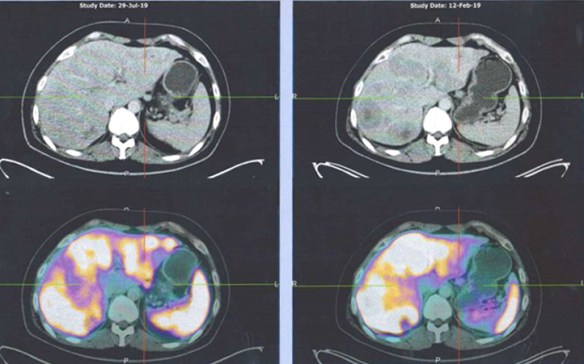

- PET scan on 14 September 2023 showed more serious condition.

- The metabolically active left lung mass with multiple neck, axillary and mediastinal nodes. Left pleura and bone lesions are likely due to primary lung malignancy.

- However, metastatic breast cancer recurrence cannot be excluded.